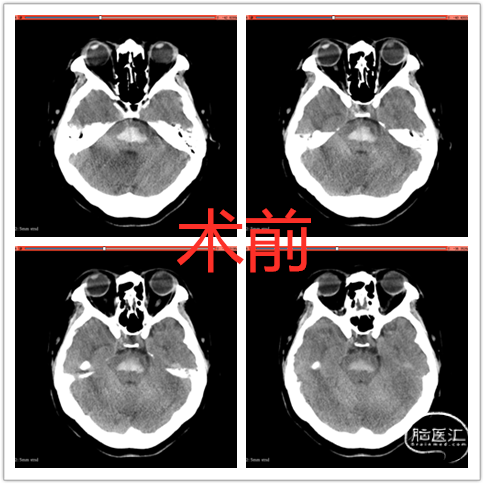

急诊CT:脑桥出血伴左侧脑桥小脑角池少许积血考虑,请结合临床,建议复查。脑动脉CTA:未见明显异常,请结合临床,必要时DSA检查。

图 1术前CT